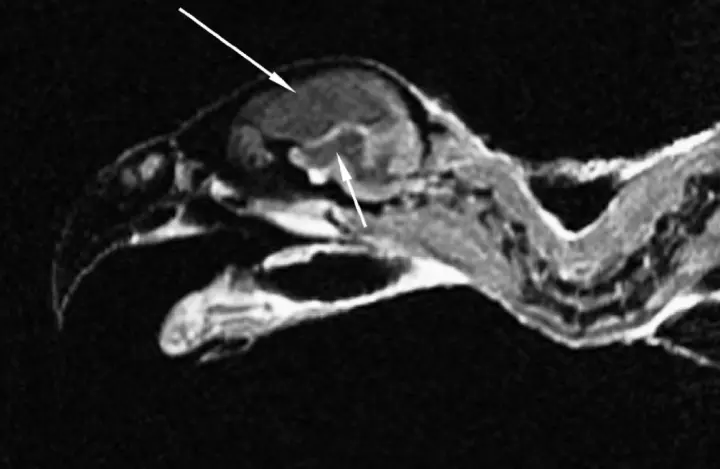

以前骂“鸟脑子”老到偏见,鸟类仅仅没走哺乳动物的“皮层路线”,东谈主家演化出了专属的“反向操作”——神经剖析层(NCL)。

这区域即是鸟类大脑的“中央处理器”,整合感知、调取挂念、作念有狡计样样行,功能跟东谈主类前额叶皮层险些没啥永别,连信息流动的逻辑齐和哺乳动物同频。

鸟类要遨游,大脑弗成太重,是以演化出了更高效的NCL区域,就像一样是智能,电脑靠硬件堆砌,鸟类却走了“诽谤自如”的捷径,足以解释聪慧的样式有多多元。